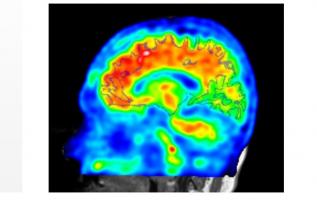

C’est un nouvel avertissement sur les conséquences de l’obésité à l'adolescence, cette fois sur la santé cérébrovasculaire, avec précisément un risque accru d'accident vasculaire cérébral (AVC) associé, à l'âge adulte. Cette très large analyse menée sur les données de près de 2 millions de jeunes adultes, âgés de 16 à 20 ans, publiée dans la revue Stroke de l’American Heart Association (AHA) conclut à un risque d’AVC précoce -avant l’âge de 50 ans- multiplié par plus de 3 chez les adolescents obèses .

L’obésité a été prise en compte à partir de l’indice de masse corporelle (IMC). L’analyse montre une relation dose-dépendante entre un IMC plus élevé à l'adolescence et le risque de premier AVC ischémique avant l’âge de 50 ans. Des résultats préoccupants alors, qu’aux Etats-Unis , lieu de l’étude, ainsi que dans un certain nombre de pays riches, les taux d'obésité sont à la hausse chez les enfants et les adolescents. Simultanément, l’incidence des AVC chez les adultes jeunes augmente également.